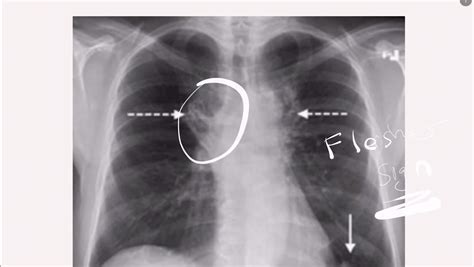

Key findings on a Pulmonary Embolism X Ray that may suggest PE include:

• Wedge-shaped opacities: These are areas of increased density in the lung tissue, often seen in the periphery of the lung.

• Pleural effusion: Fluid accumulation in the pleural space, which can be a sign of inflammation or infection.

• Enlarged pulmonary arteries: Dilatation of the pulmonary arteries, which may indicate increased pressure due to a clot.

• Atelectasis: Collapse or incomplete expansion of the lung tissue, which can be a sign of obstruction.

However, it is important to note that these findings are not specific to PE and can be seen in other conditions. Therefore, further diagnostic testing is often required to confirm the diagnosis.